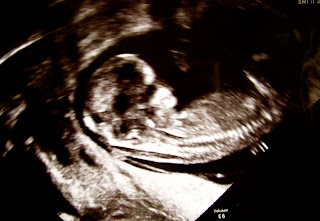

Viikolla 12 koitti suuri onnen päivä. Pääsin näkemään, miten tyttö on kehittynyt. Ultraaja levitti geeliä avopuolisoni vatsalle ja asetti anturan. Näytölle ilmestyi alkiovaiheessa oleva kala, ja niin sitä mentiin. Avopuolisoni valahti kyyneliin. Vatsan ihon läpi näkyi ihme, oma vauva.

Mutta minuapa odotti elämäni järkytys. Sikiön sukupuoli oli väärä. Sikiö olikin poika.

Se oli isku päin kasvoja. Kysyin änkyttäen, miten suuri osuus sukupuolen selvittämisessä on Ultraajan subjektiivisella tulkinnalla. Ultraaja vastasi, että selvästi erottuva pippeli haarojen välissä ennustaa vahvasti poikalasta.

Toisessa ultrasessiossa viikolla 20 pippeli oli kasvanut. Olin järkyttynyt. Ei: olin kauhuissani. Koko elämäni olin valmistautunut kasvattamaan tyttöjä. Olin valmis tytön isäksi. Mutta entä poika? Poika josta joskus kasvaa mies? Miten kaltaiseni mies pystyisi kasvattamaan pojan tosimieheksi? Mieheksi, joka selviää hengissä miesten maailmassa, jossa herkkyydelle tai kaunosieluisuudelle ei ole tilaa. Miesten maailmassa ne on kätkettävä. On kasvatettava panssari. Muuten päätyy koulukiusatuksi. Itse olen tarvittaessa osannut vetää ylleni äijänaamarin. Mutta osaako poikani? Oppiiko hän tasapainoilemaan herkkyyden ja kovuuden välillä? Elämässä pitää tietää, milloin kannattaa uida petokalaa karkuun ja milloin piiloutua silliparven keskelle. Oppiiko hän olemaan oma itsensä saamatta päivä toisensa jälkeen turpaan?